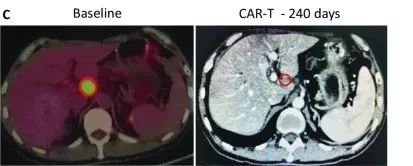

典型病例

受试者GD-G/M-005 是一例具有 MSLN 表达的晚期胰腺癌患者。该受试者进展为局部淋巴结转移(24×33 mm)(图c)。抗 MSLN-7 × 19 CAR-T 细胞首先通过肝动脉输注,当晚伴有高烧,没有细胞因子释放综合征 (CRS) 或神经毒性。随后,他每1~2个月接受一次抗 MSLN-7×19 CAR-T 细胞的静脉输注。

直到增至CAR-T细胞输注的5倍,CT分期显示他在治疗240天后达到完全缓解,测定的淋巴结为8.3×9.6mm,并未见其他肿大的淋巴结(图C),患者此时病灶完全消失,保持正常状态。